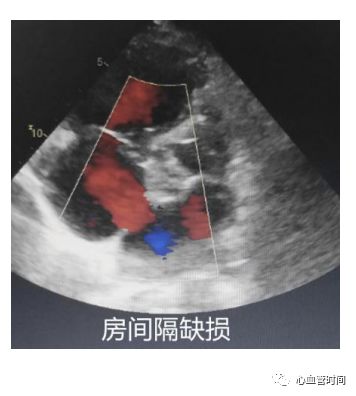

房间隔观察有无过隔血流、膨出瘤及摆动现象。一定要注意区分右房内的

红色血流是起源自下腔静脉还是房间隔,避免误诊。

房间隔观察有无过隔血流、膨出瘤及摆动现象。一定要注意区分右房内的

红色血流是起源自下腔静脉还是房间隔,避免误诊。

房间隔当存在

房间隔缺损时,过隔血流因几乎垂直于探头而不易观察,建议可稍微

偏转探头调整血流角度进行观察。

房间隔当存在

房间隔缺损时,过隔血流因几乎垂直于探头而不易观察,建议可稍微

偏转探头调整血流角度进行观察。

剑突下切面

对于一些胸前切面显示不清的患者,剑突下切面可以很好地 作以补充。 房间隔 在患者成像条件良好的前提下,剑突下切面是观察 房间隔缺损的绝佳切面。该切面房间隔相对垂直于探头,可更好的显示 过隔血流,像卵圆孔未闭的几毫米的血流也能轻松显示,且可更好的与腔静脉的血流做区分,明确血流来源。 下腔静脉